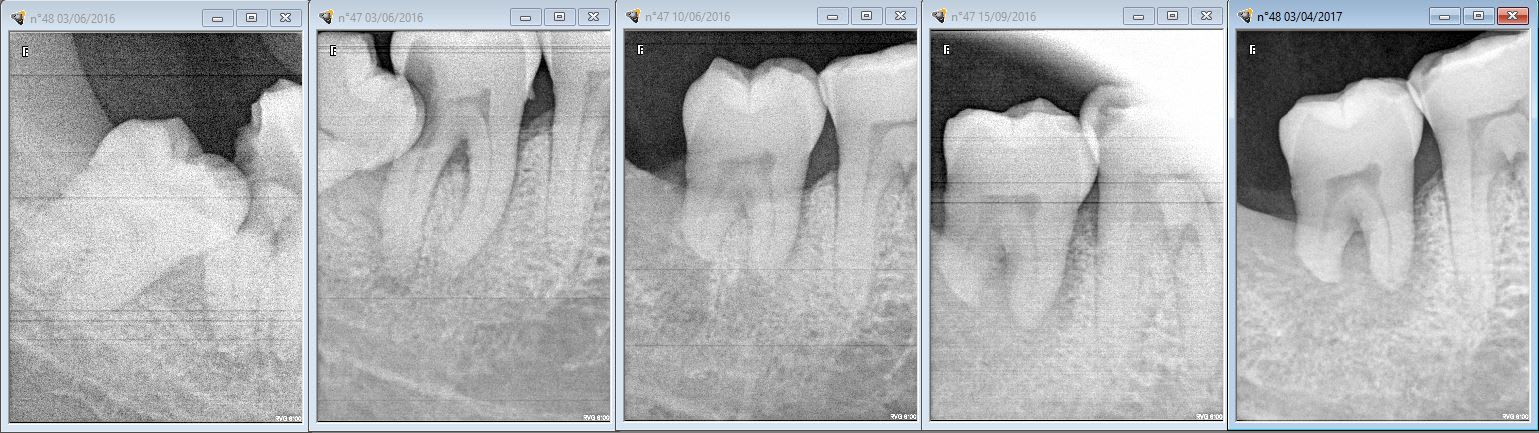

controle de la dent de la page 8

Hoho! entre la page 8 et la page 22 tu as changé la couronne!

oui tres rapidement apres l'époque de la page 8 .

Comme je vois que tu boudes Enlaye , je te réveille en publiant ma ERI de 48 à la place de la 47 ! Alors, comme ce patient est un météore , il vient , ne vient plus , aujourd'hui il se pointe avec une 37 fendue en 2 de haut en bas ! Dent intacte ! Bref j'ai jamais réussi à lui faire l'endo de cette 48 . Alors elle est mobile bien sur , mais sans symptome . J'espère pourvoir faire l'endo d'ici 15 jours mais c'est pas gagné ! en tout cas pas trace de résorption !